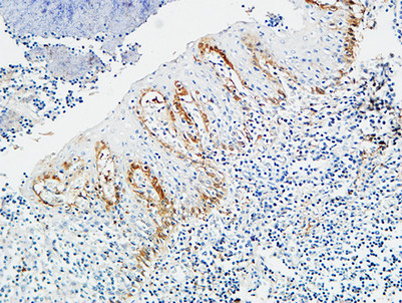

Product name: Pax-8 rabbit pAb

Dilutions: Western Blot: 1/500 - 1/2000. Immunohistochemistry: 1/100 - 1/300. ELISA: 1/10000. Not yet tested in other applications.

Immunogen: The antiserum was produced against synthesized peptide derived from human Pax-8. AA range:145-194

Background: This gene encodes a member of the paired box (PAX) family of transcription factors. Members of this gene family typically encode proteins that contain a paired box domain, an octapeptide, and a paired-type homeodomain. This nuclear protein is involved in thyroid follicular cell development and expression of thyroid-specific genes. Mutations in this gene have been associated with thyroid dysgenesis, thyroid follicular carcinomas and atypical follicular thyroid adenomas. Alternatively spliced transcript variants encoding different isoforms have been described. [provided by RefSeq, Mar 2010],